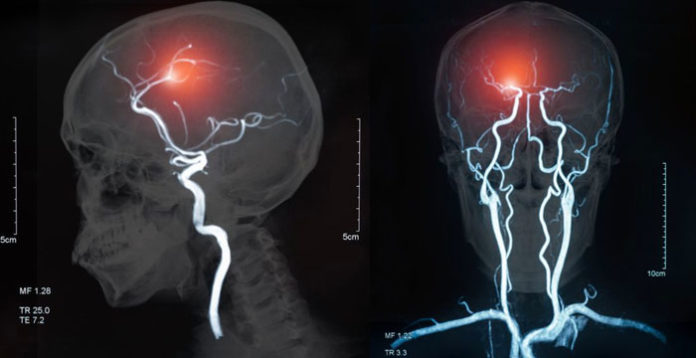

Las personas con diabetes tipo 2, pero no aquellas con prediabetes, tuvieron un rendimiento cognitivo peor de tres a seis meses después de un derrame cerebral que aquellas con niveles normales de azúcar en la sangre en ayunas, según una nueva investigación publicada hoy en Stroke, una revista de la American Stroke Association, un división de la American Heart Association.

Los investigadores combinaron datos de 1,601 pacientes con accidente cerebrovascular (edad promedio 66; 63% hombres; 70% asiáticos; 26% blancos; 2.6% afroamericanos) que participaron en uno de los siete estudios internacionales de seis países. Casi todos tenían accidentes cerebrovasculares causados por coágulos, y se evaluaron una variedad de funciones cognitivas entre tres y seis meses después del accidente cerebrovascular. Los niveles de azúcar en sangre en ayunas de los pacientes medidos al ingreso hospitalario y el historial médico se utilizaron para definir la diabetes tipo 2 y la prediabetes.

En comparación con los pacientes con niveles normales de azúcar en sangre en ayunas, aquellos con diabetes tipo 2 obtuvieron puntajes significativamente más bajos en diferentes áreas de la función cognitiva, incluida la memoria, la atención, la velocidad de procesamiento de la información, el lenguaje, la capacidad visual para copiar o dibujar formas o figuras o líneas, flexibilidad mental y funcionamiento ejecutivo.